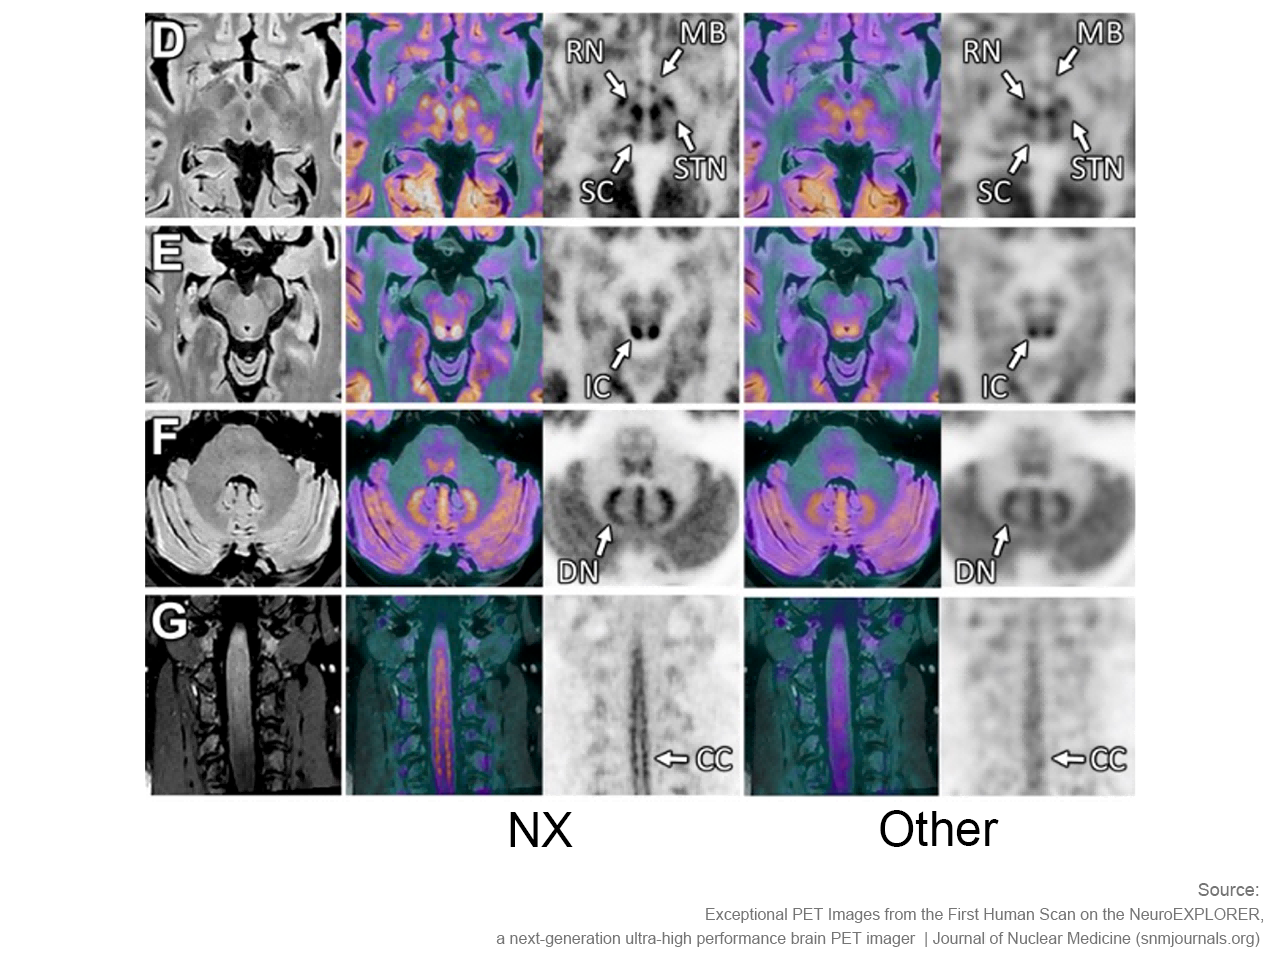

NeuroExplorer (NX)产出的脑部影像图

NeuroExplorer拥有基于NEMA NU 2-2018标准的超高灵敏度:46cps/kBq,同时配备着先进的时间飞行技术,进一步增强了NX的综合性能。

小型探测器元件确保最精微的结构能被检测,甚至探查特定脑核中的神经递质运动。搭载1.5mm的有效空间分辨率,带来前所未见的解剖细节。

NeuroExplorer (NX)产出的脑部影像图与其他设备产出的脑部影像图对比

一直以来,运动伪影困扰着核医学界,扫描过程中患者任何轻微移动都会对最终的图像清晰度产生影响。NX革命性地开发实时无标注头部运动追踪,解决了头部运动造成的成像伪影问题,确保成像卓越精度。

“从我们目前获取的图像来看,使用NeuroExplorer扫出的图像是世界上最好的,因此我们能够真正做到更好地缩小范围,聚焦更小的信号,观察大脑更为微末的区域,这为我们打开了新的窗口,去‘见所未见’。”Carson教授对NX的诞生和即将围绕其展开的一系列研究满怀期待,“有了NeuroExplorer这样强大的设备,我们步履不停,也正将迎来一个重要的突破,那就是和制药行业的合作。”